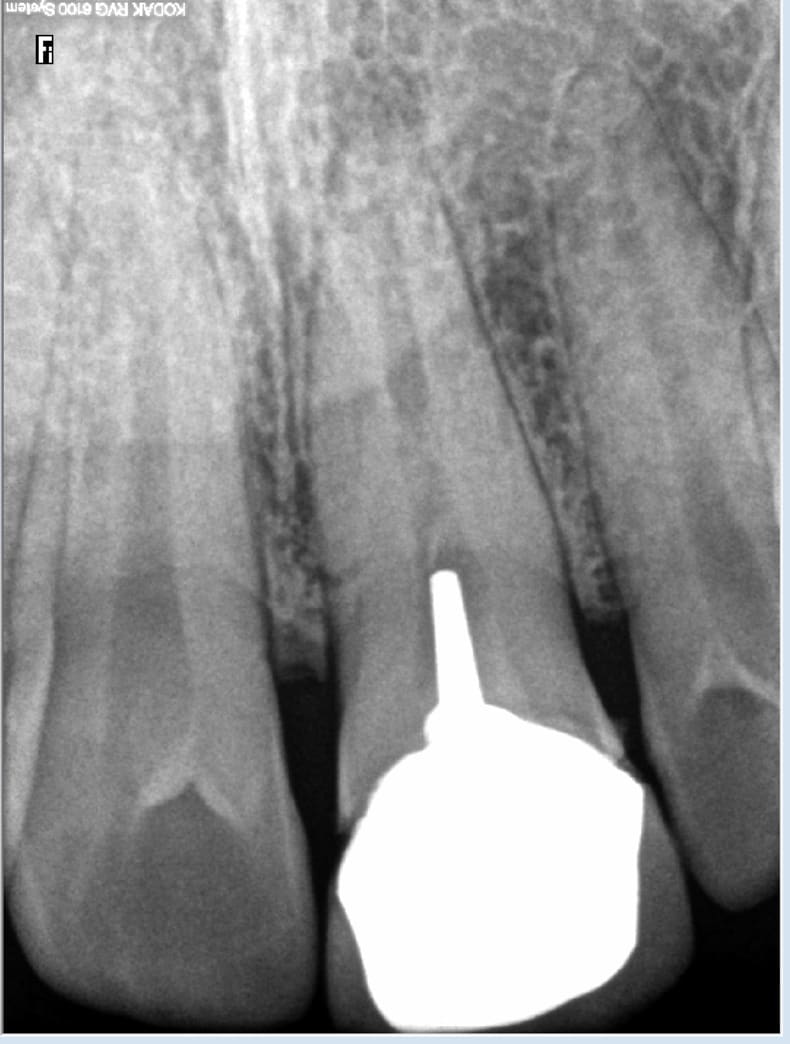

Le mec, il avait une denture parfaite, la seule fois où il est allé voir un dentiste pour faire un soin, probablement suite à un trauma, on lui a fait un travail de merde. Et à la fin, celui qui rend des comptes, c'est celui qui fait un status. Vive la France!

Tu l'as un peu mauvaise. D'un autre coté ça accélère tes connaissances en indications radios. J'ai du bol en plus j'ai plus de pano sinon ca aurait été un carnage. Indication signe d'appel : trauma antérieur. -)))